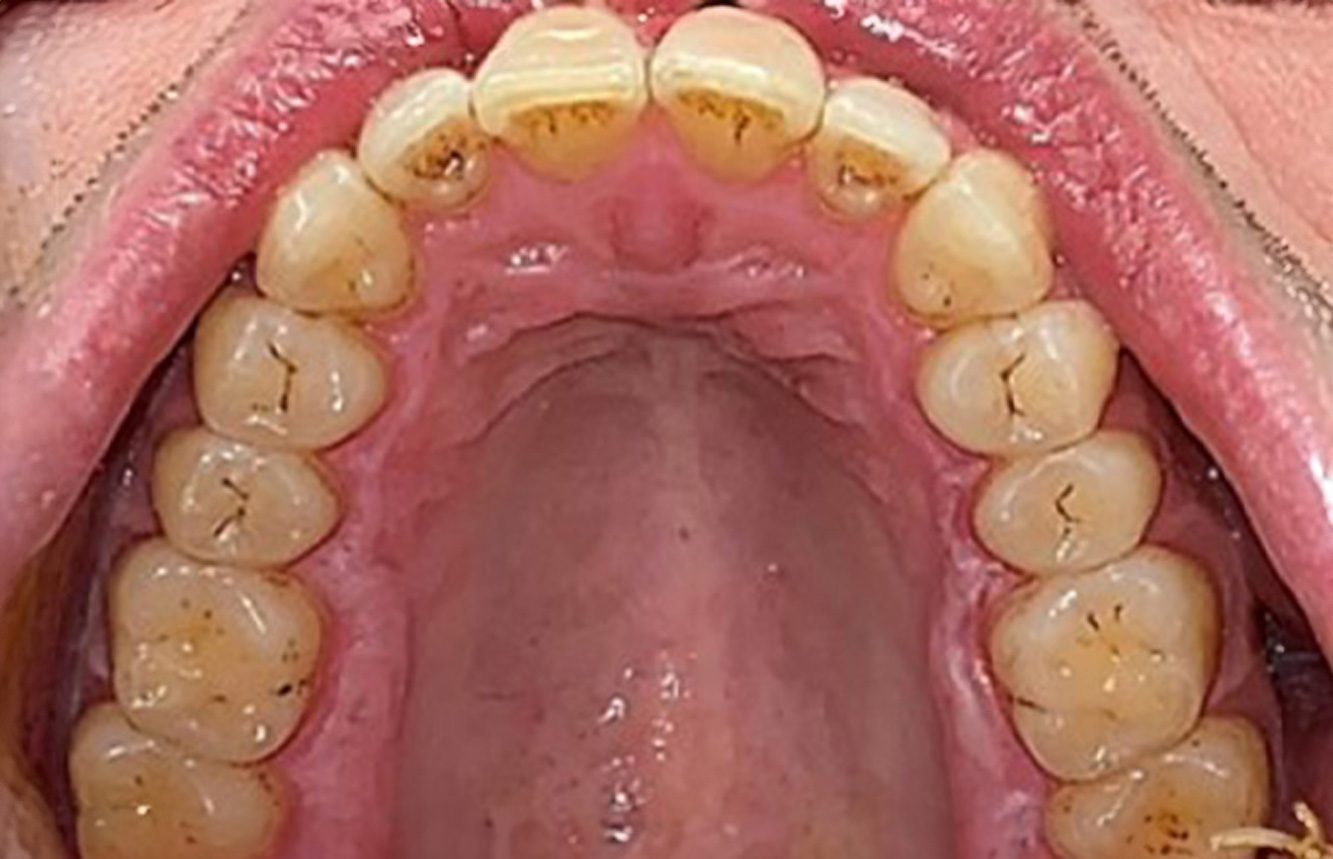

The transplant patient with gingival overgrowths

A 71-year old patient presents with having previously undergone a kidney transplant and with a history of hypertonia (high blood pressure). Due to his medical history, long-term medication with cyclosporine is required to suppress the immune system, as well as amlodipine to lower blood pressure. The patient also reports sensitive and bleeding gums. From an oral health perspective, the patient has undergone dental restoration and has eight missing teeth, pronounced gingival growth, and grade B, stage II periodontitis with active pockets and initial root caries on tooth 22. The caries risk assessment determines a moderate risk of caries (API 60). The following treatment recommendations can be determined for the prophylaxis session. more